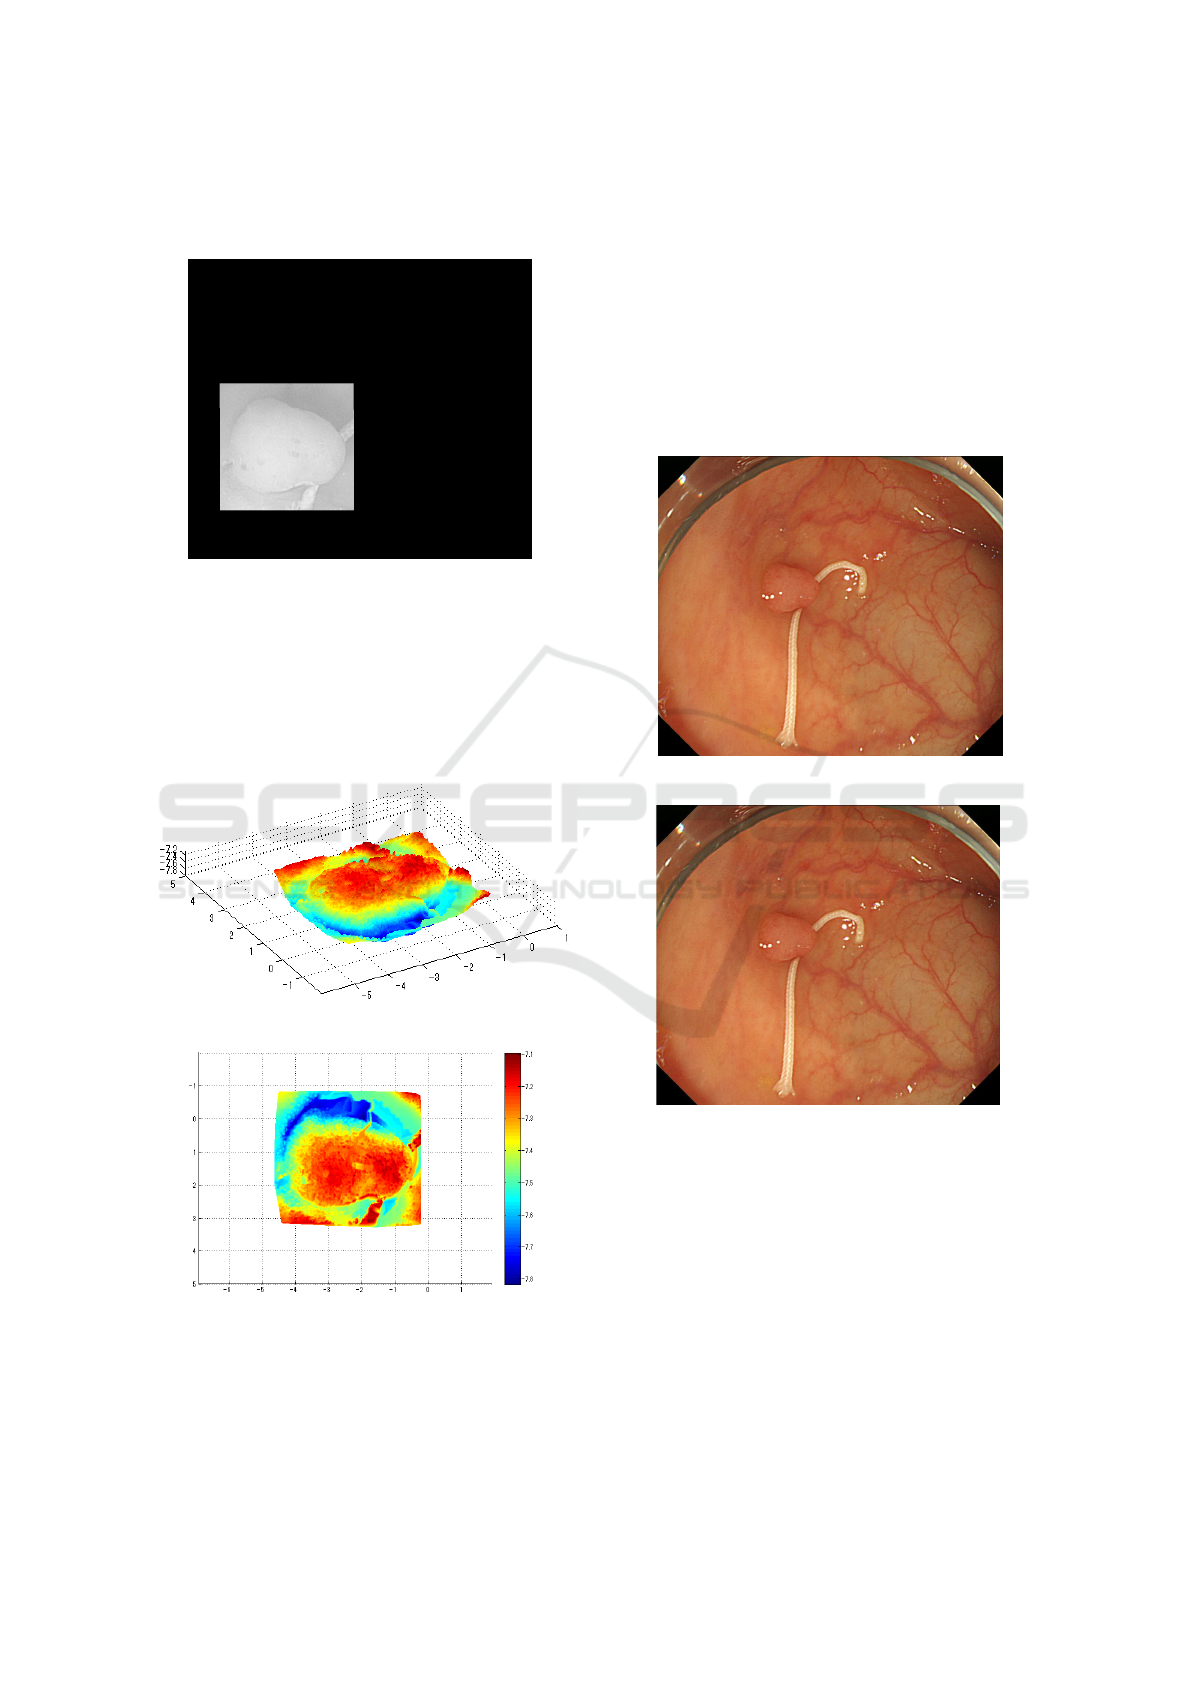

adding the medical suture as a calibration object with

known size. The approach essentially solved the

problem of treating the camera movement as known

constant under the condition that the original image

is converted to Lambertian image by removing spec-

ular reflectance with uniform reflectance parameter.

Based on estimating ∆Z, it makes possible to esti-

mate the reflectance parameter C and further to re-

cover the absolute size and shape of polyp based on

Shape-from-shading approach.